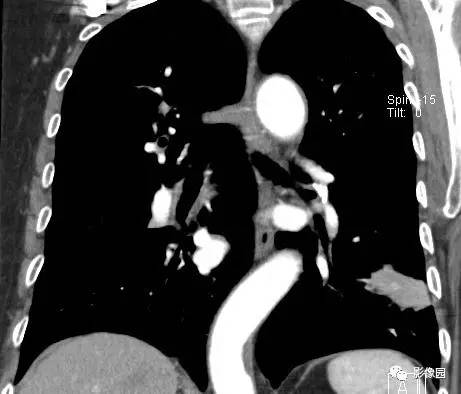

左下肺鳞癌1例CT

病史:女,77,体检发现左下肺占位5天。CT平扫肿物CT值约为40Hu,增强后约95HU 医学百科网 | YxBaike.Com

穿刺结果:(左下肺)部分肺组织:慢性支气管炎及支气管周围炎,肺泡间质纤维组织增生,个别支气管粘膜鳞状上皮化生,部分恶变,呈鳞状上皮原位癌结构,极个别区域有支气管壁早期浸润。 医学百科网 | YxBaike.Com